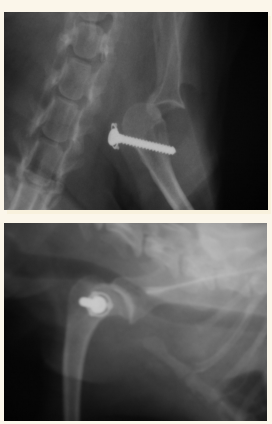

Cadera

En general se hacen proyecciones:

- Ventro-dorsal: Extender extermidades y traccionar, sin rotación axial, paralelas a la mesa, buscamos que la rotula se superponga con el surco troclear. Posicion de rana si es una fractura pelvica

- Latero-Lateral: Esponja de gomaespuma entre rodillas, estirar extermidades posteriores a caudal

Problemas mas comunes:

- Displasia

- Luxación sacroilíaca

- Luxación coxo-femoral

- Fracturas articulares

- Necrosis avascular de la cabeza femoral

- Fracturas pélvicas (generalmente múltiples y afectan a tejido blanco coetáneo)

- Necrosis avascular de la cabeza femoral (Enf. de Legg-Calvé-Perthes) IMPORTANTE, LO SUELE PREGUNTAR

Luxación Coxo-femoral

- Por traumatismo, a veces leve si existe Displasia. Suele aparecer con fracturas de pelvis, uni o bilateral

- Normalmente cráneo-dorsal, aunque puede ser dorsal, ventral, caudal (rara) o intrapélvica

- Mejor 2 proyecciones pero en VD se ve mejor (ilion desplazado, mayor tamaño articular, perdida de contorno liso)

- Tambien hay luxacion sacro iliaca.

- Hay que ver la direccion de la luxacion. La mas frecuente es craneo-dorsal pero hay mas.